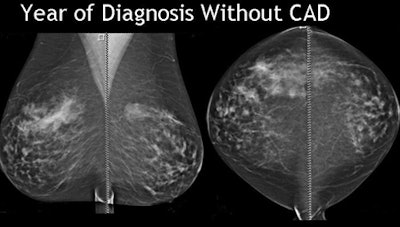

![]() |